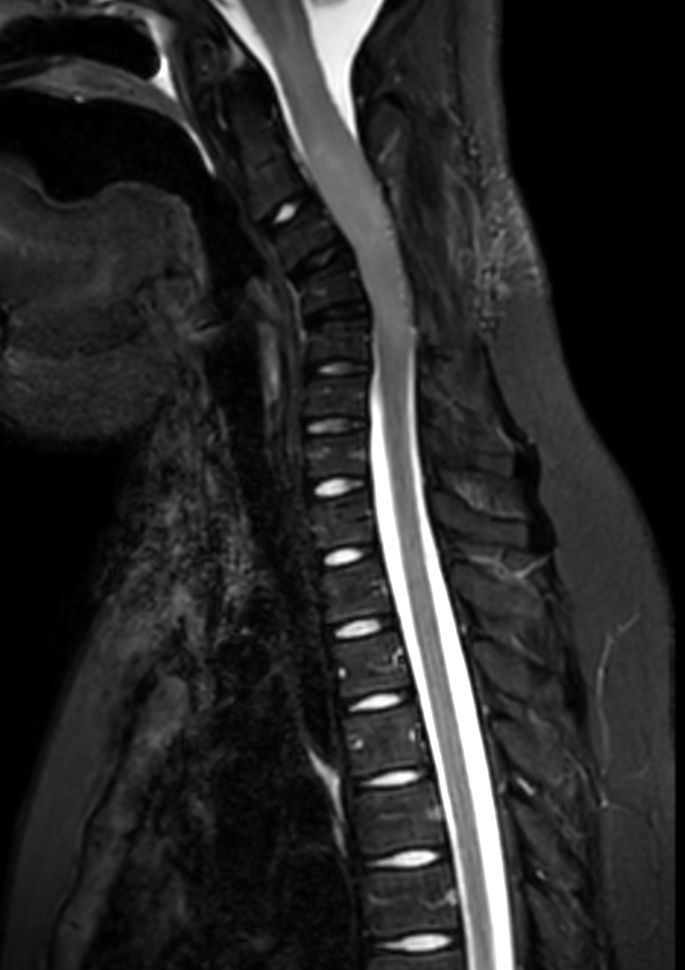

Sagittal T2w TSE (C-Spine)